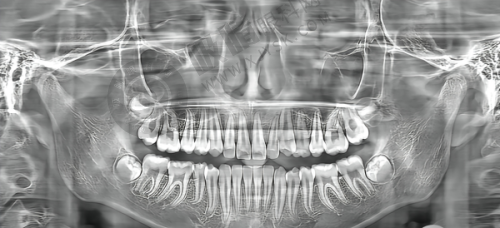

这是赛德阳光口腔的主要特色项目,在赛德阳光口腔·广州明德口腔门诊部也不例外。医生会根据患者的牙齿情况,如牙齿拥挤、龅牙、地包天等不同问题,制定合适的正畸方案。常见的正畸方式有金属托槽矫正、陶瓷托槽矫正、隐形矫正等。